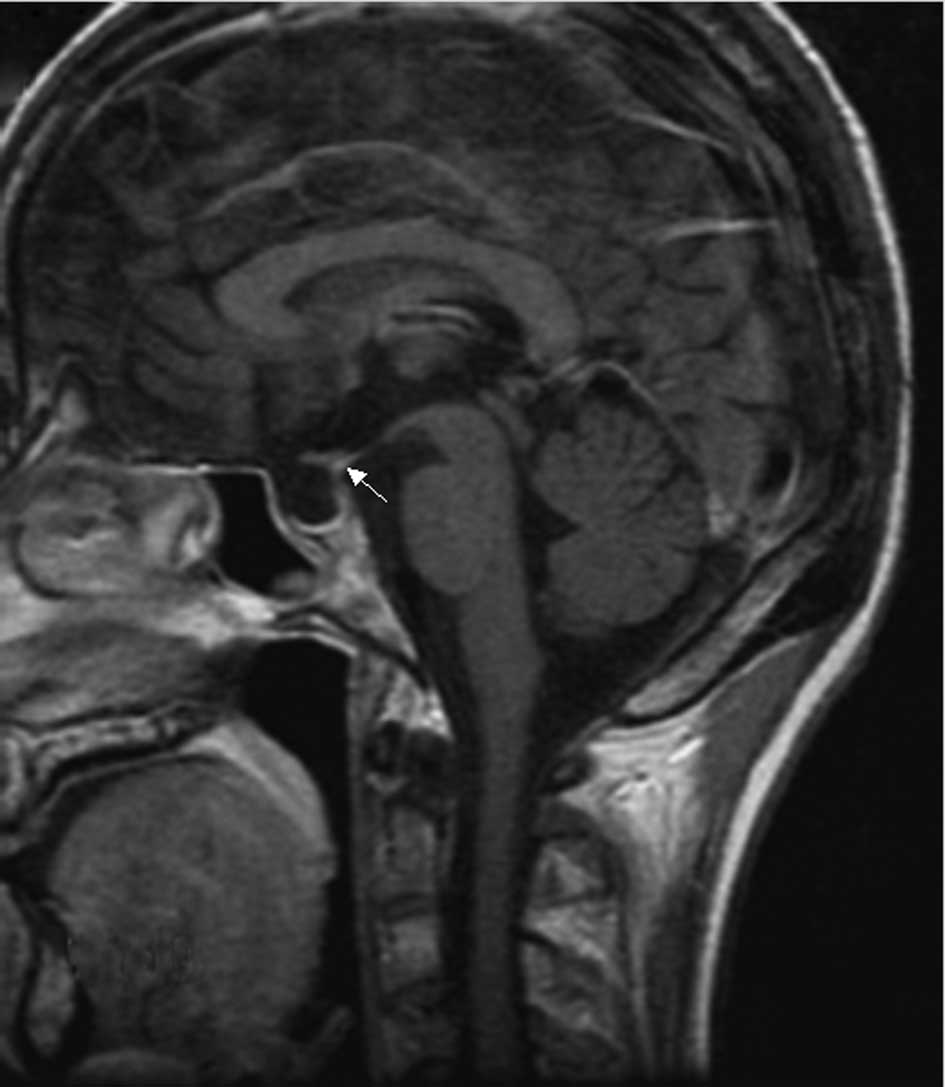

Non-enhanced magnetic resonance image (MRI) of the sagittal section of patient 2 showing the disappearance of the characteristic high signals of the posterior pituitary and increased size of the pituitary stalk.

Figure 4

The MRI of the patient 2 revealed that the hypophyseal fossa was small and the high signals from the posterior pituitary had disappeared. Notably, enhanced CT of the chest and abdomen showed bad bilateral perfusion in the kidneys that may have been associated with diffuse and infiltrative tumors.